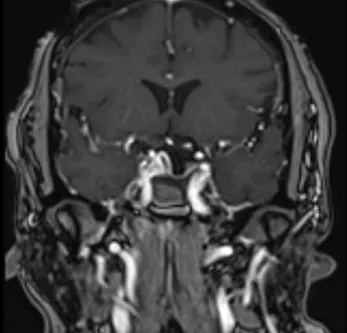

Pre- and Post-Op Pituitary Macroadenoma

Post-Op Image of Pituitary Tumor 1

Post-Op Image of Pituitary Tumor Surgery